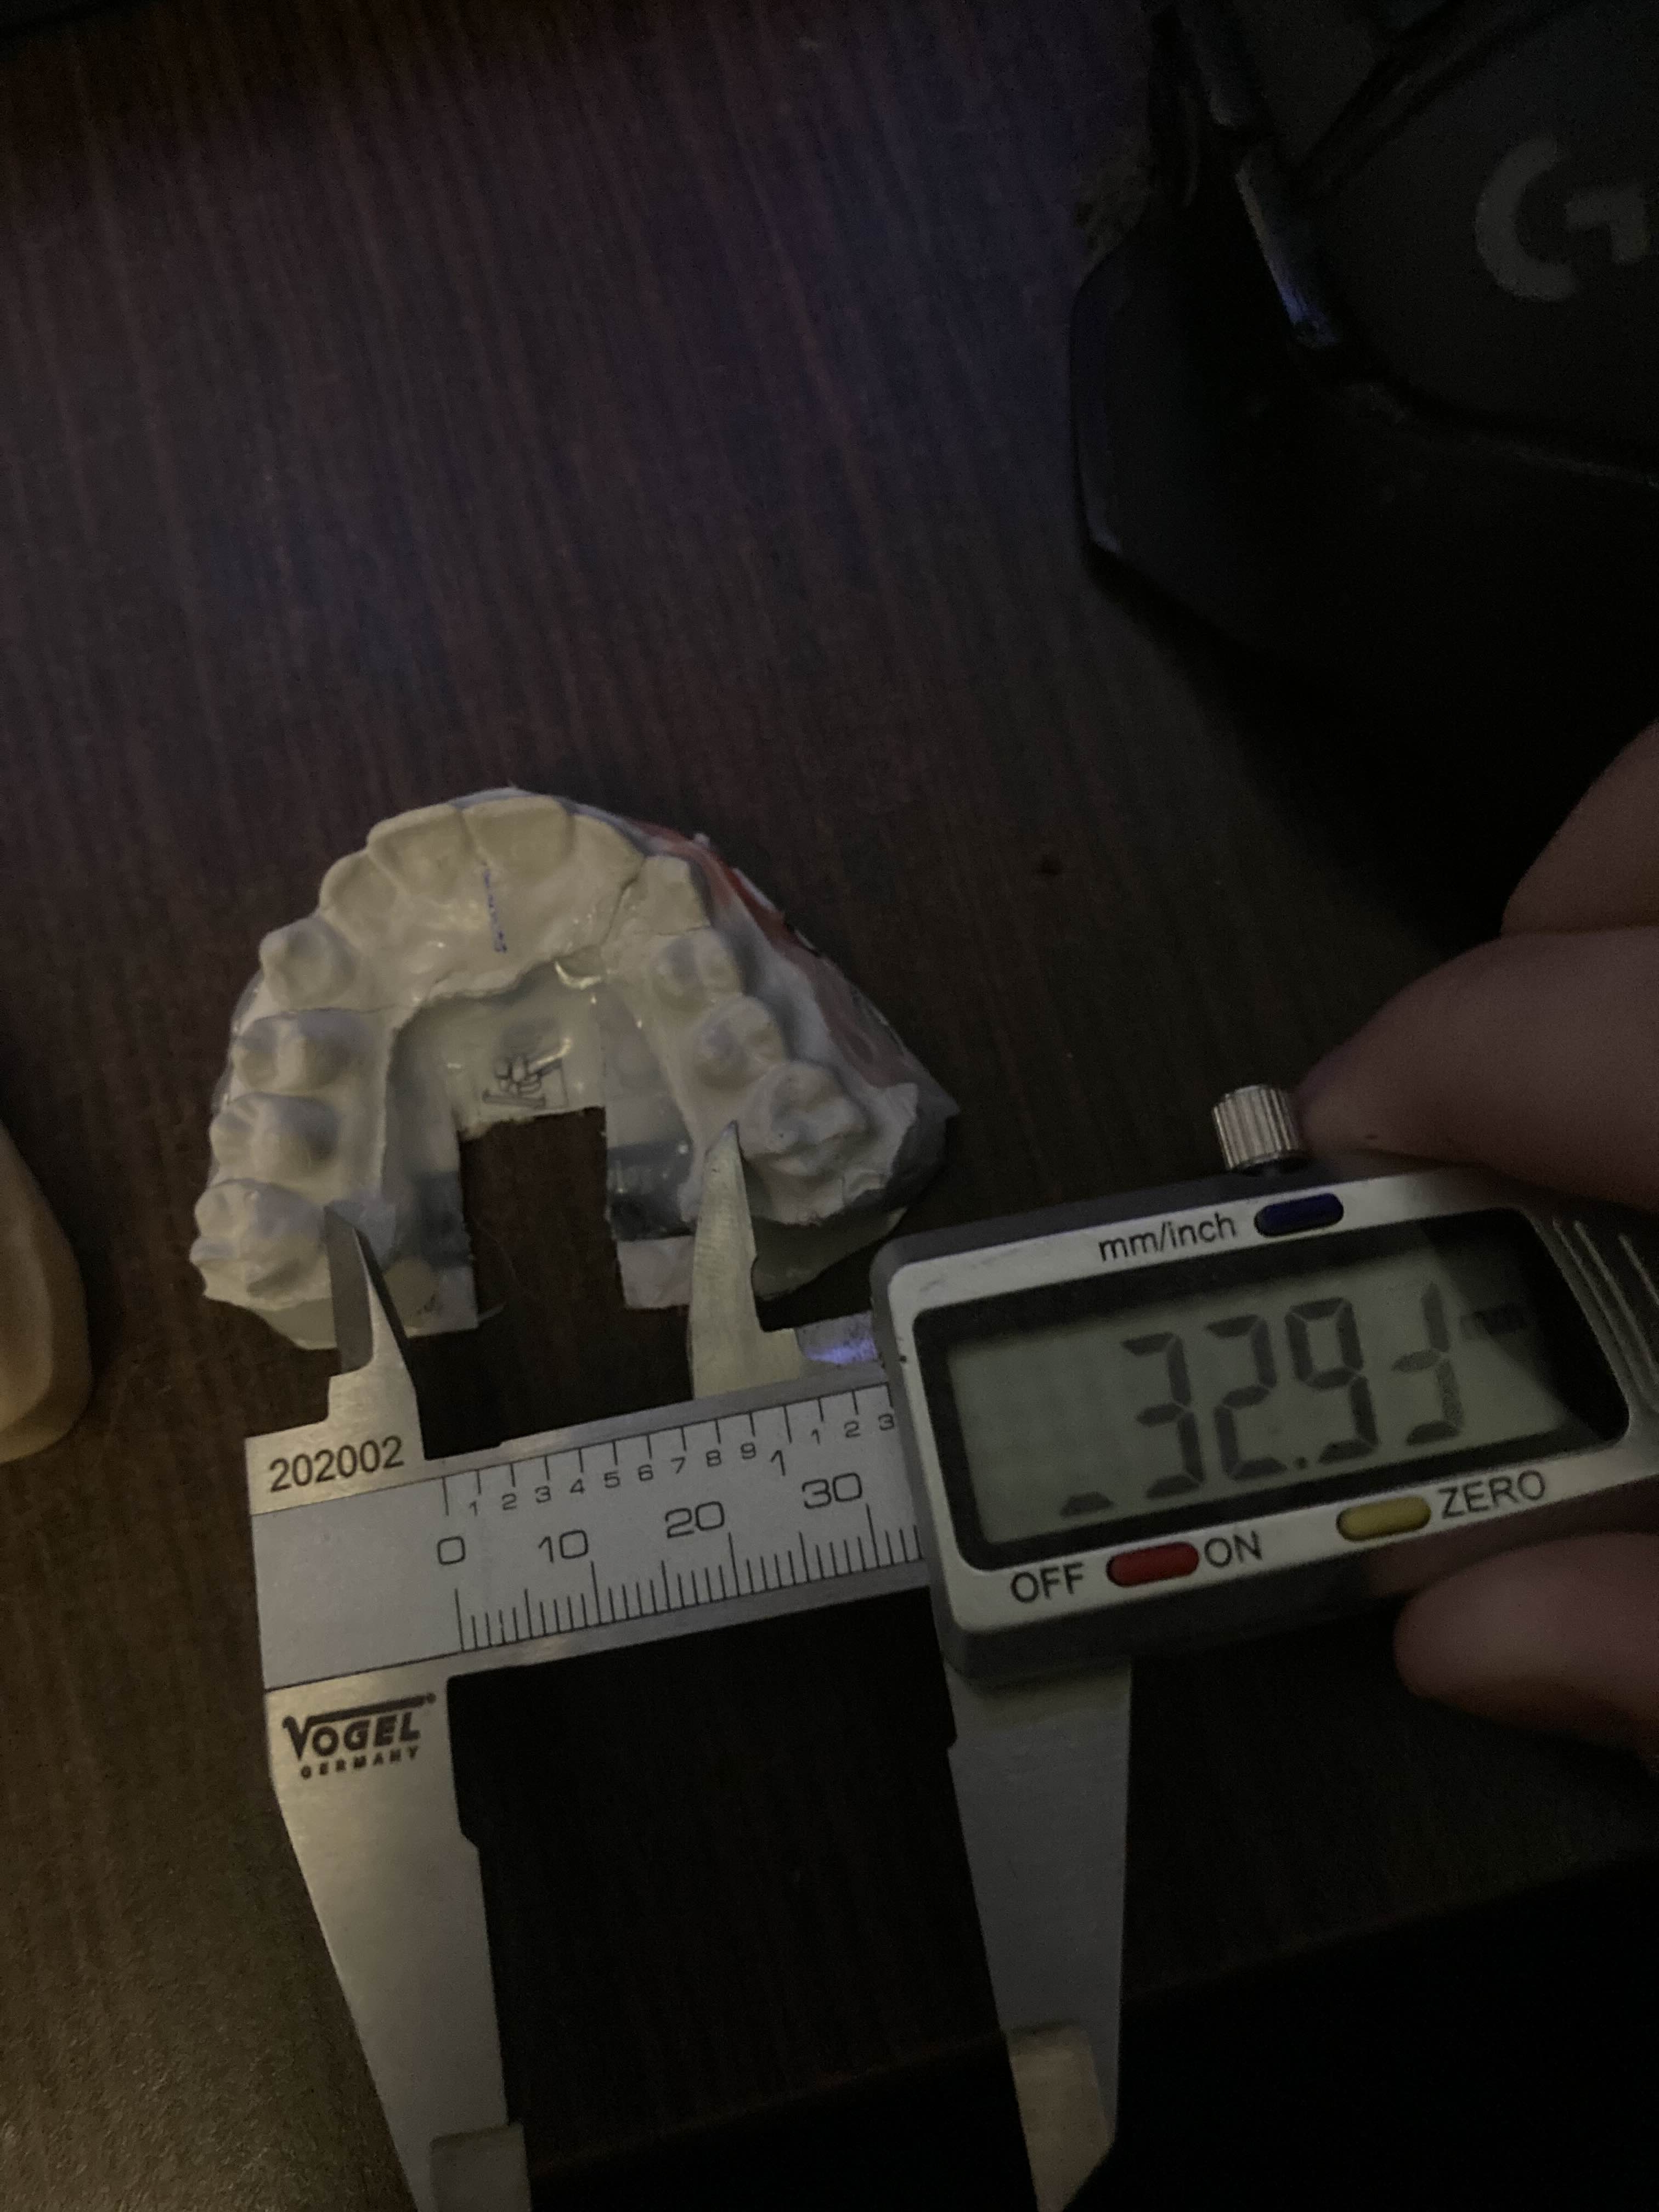

The white mold was made by me the yellow by them very quality stuff I must say

The white mold was made by me the yellow by them very quality stuff I must say